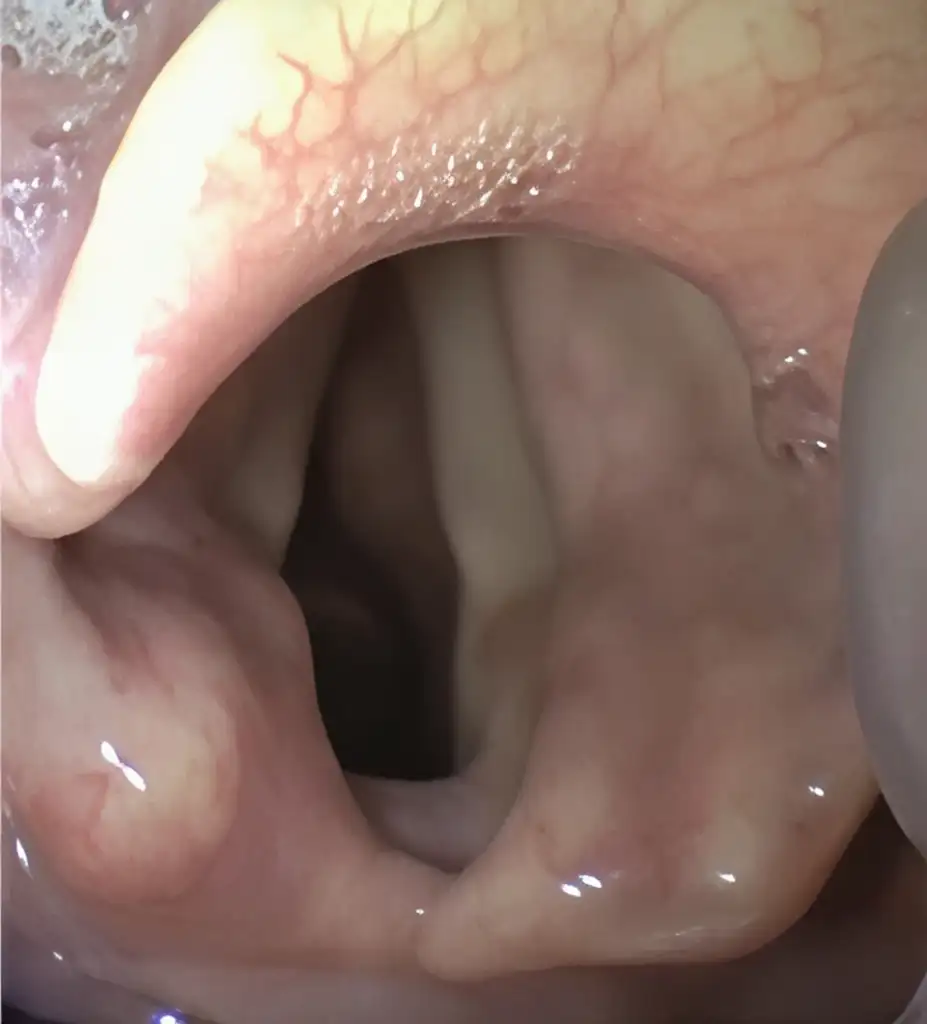

MacIntosh Blade in the Vallecula (preferred)

Airtraq allows both techniques

Macintosh style is the preferred option since it requires less upward traction and therefore it is softer on patient tissues.

If the Airtraq is already underneath the epiglottis and the user prefers to intubate Macintosh style withdraw the Airtraq until the epiglottis falls and advance the tip of the blade into the vallecula.

Miller Blade underneath Epiglottis